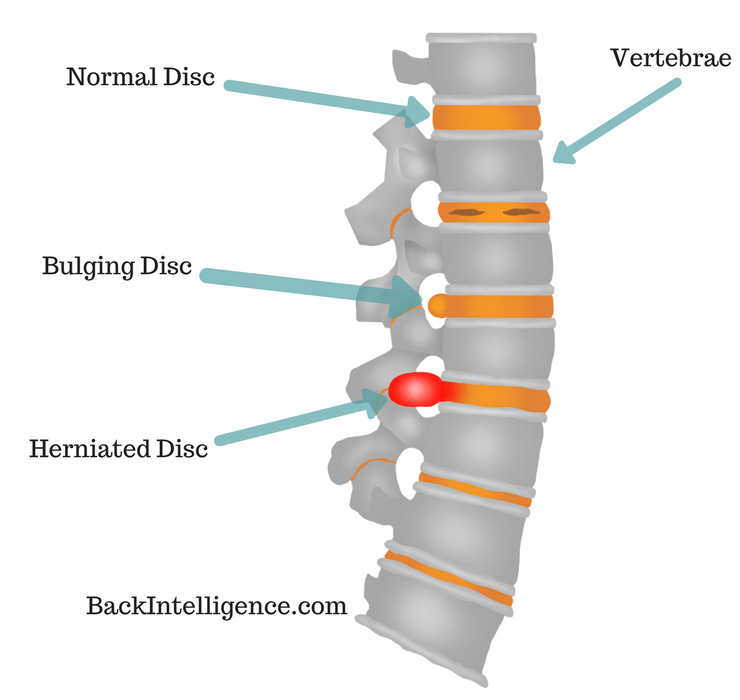

What is the difference between a bulging disc and a herniated disc?